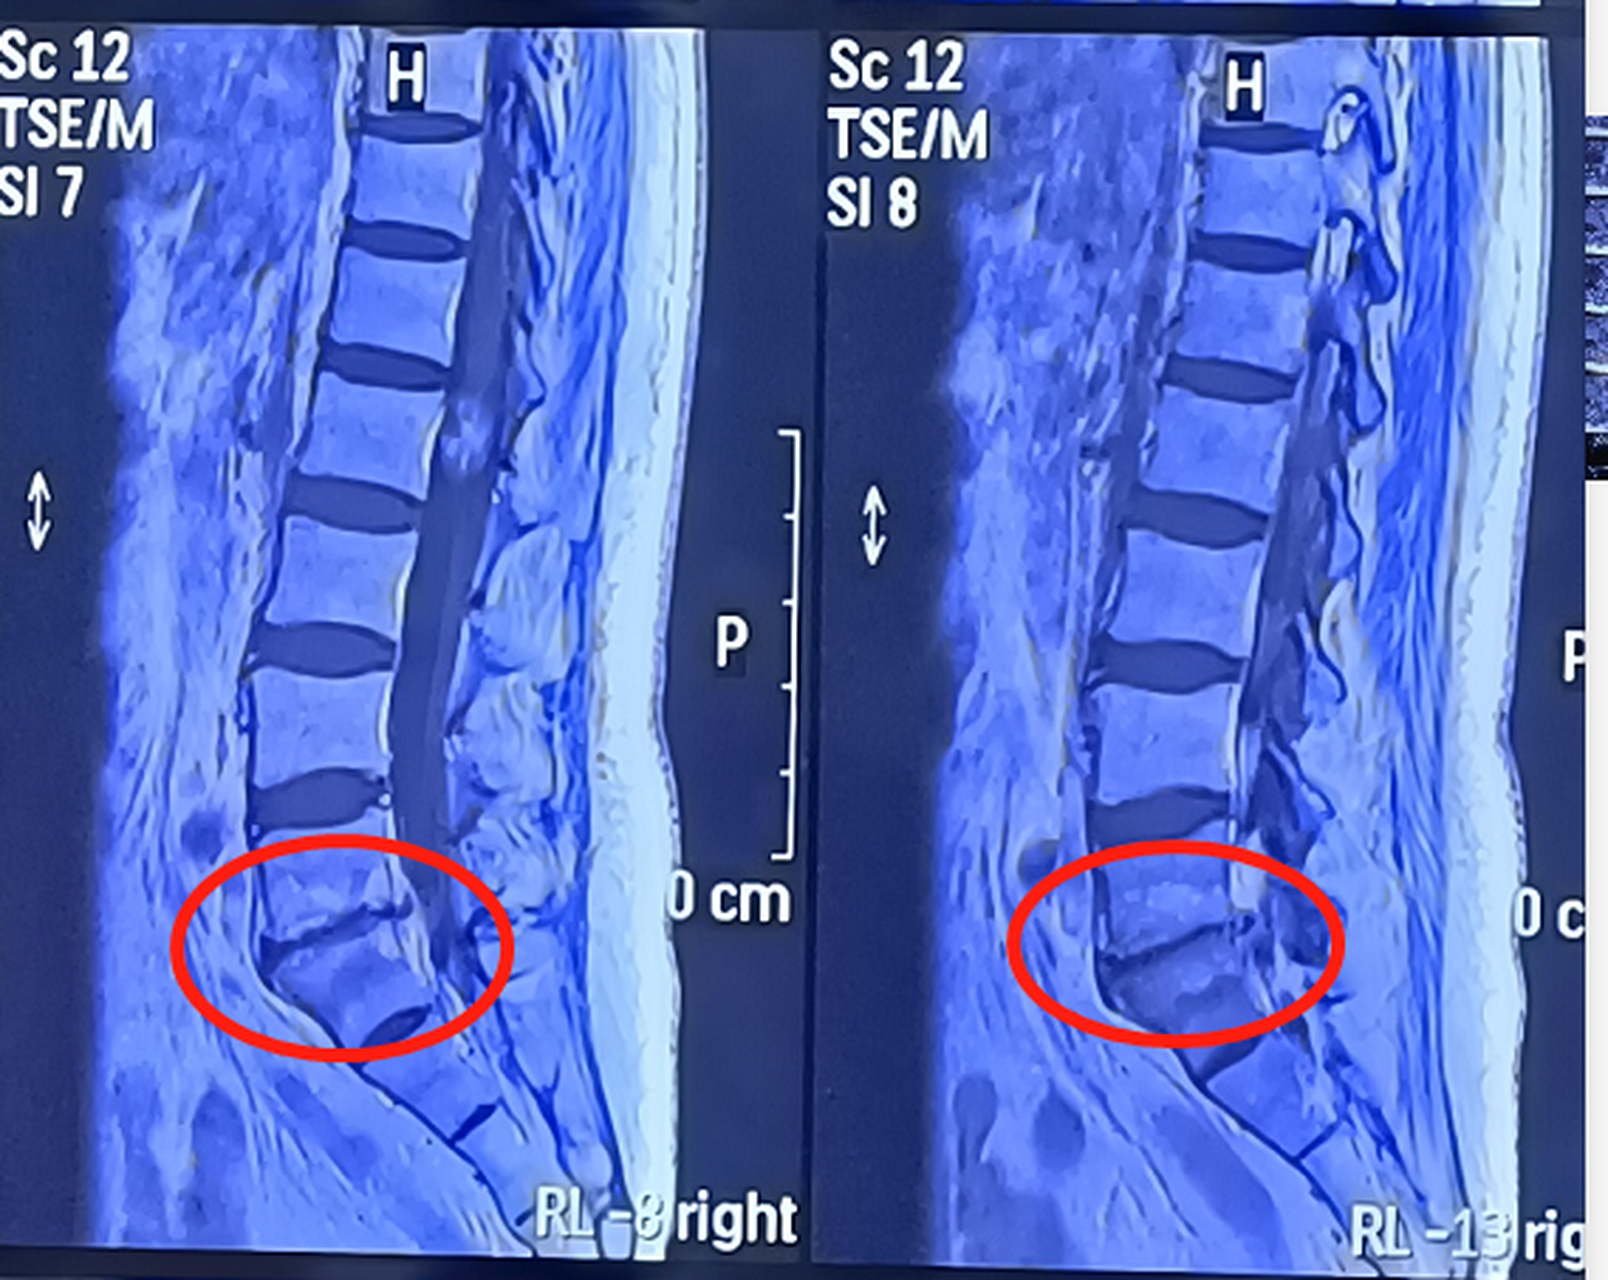

腰椎ct 有没有医生帮忙看看腰椎ct这个样子严重吗?

间盘核磁共振椎体终板炎影像学表现骨钙化终板炎图片ct终板炎诊断图片

腰椎ct平扫可见其l5s1节段为严重的终板炎(图中箭头所示).

腰椎ct